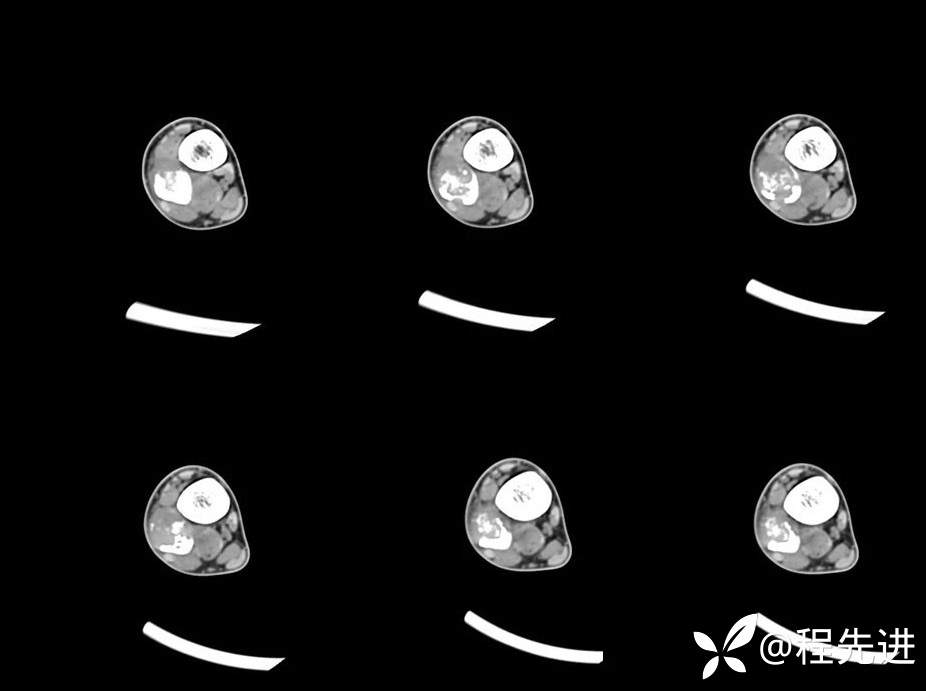

CT平扫

CT平扫、增强动脉期、静脉期

平扫67HU、动脉期81HU、静脉期93HU